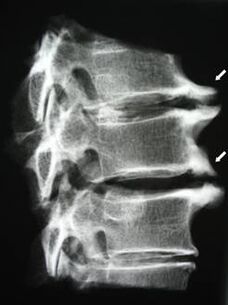

Algstaadiumis tuvastatakse MRI abil osteokondroos. Hiljem saab patoloogiat diagnoosida radiograafia abil. Emakakaela lülisamba röntgenülesvõtetel on märgatav selgroolülide vahelise kauguse vähenemine, patoloogilised muutused tahk liigestes ja osteofütoos.

| Emakakaela osteokondroos | Patoloogiliste muutuste ilmnemine ühes või mitmes selgroo liikumise segmendis. Lülisamba liikuvuse halvenemine, müofastsiaalsete valusündroomide teke ja seljaaju juurte pigistamine | Valu, paresteesia ja motoorsed häired emakakaela piirkonnas, mis levivad pea taha ja ülemistele jäsemetele. Lülisamba iseloomulike muutuste tuvastamine MRT-l ja radiograafial (osteofüüdid, selgroolülide vahekauguse vähenemine, selgroolülide kahjustuse tunnused) |